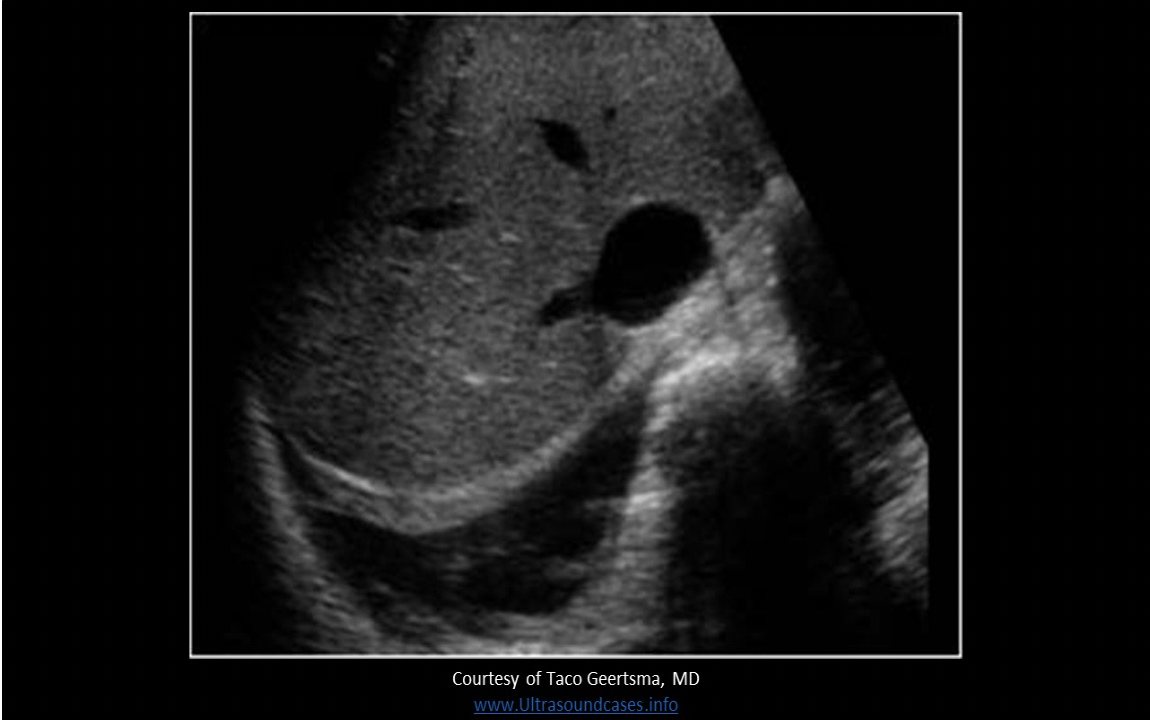

Where is free fluid documented on the image?

A. pleural space

The image demonstrates a fluid above the diaphragm in the RUQ. There is moderate pleural effusion present in the pleural space.